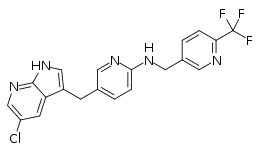

Because TAM CSF1R signaling is tumor-permissive and can tumor treatment-resistance, CSF1R signaling is a promising therapeutic target in the treatment of cancer. Several studies have investigated the efficacy of CSF1R inhibitor as a monotherapy and as a combination therapy in refractory and metastatic cancers. Several small molecule inhibitors and monoclonal antibodies targeting CSF1R are in clinical development for cancer therapy (Table 2). Pexidartinib (PLX3397) is a small molecule inhibitor tyrosine of CSFR (as well as cKIT, FLT3, and VEGFR) with the most clinical development so far. Several completed and concurrent clinical trials have tested the efficacy and safety of Pexidartinib as a monotherapy for c-kit-mutated melanoma, prostate cancer, glioblastoma, classical Hodgkin lymphoma, neurofibroma, sarcoma, and leukemias.[16] In 2019, Pexidartinib was FDA-approved for treatment of diffuse-type tenosynovial giant cell tumors, a non-malignant tumor that develops from synovial tissue lining the joints.[24]

| Pexidartinib (PLX3397) | Small molecule | CSF1R, c-KIT, VEGFR, and Flt3 | Autoimmune diseases, Alzheimer's disease, Leukemia, acral melanoma, mucosal melanoma |

| PLX5622 | Small molecule | CSF1R | Rheumatoid arthritis, cancer, neuropathic pain, Alzheimer's disease |

| Sotuletinib (BLZ945) | Small molecule | CSF1R, c-KIT, PDGFRβ, and Flt3 | Solid tumors, amyotrophic lateral sclerosis |

| GW2580 | Small molecule | CSF1R | Arthritis, osteoporosis, cancer |

| Ki20227 | Small molecule | CSF1R, VEGFR2, c-KIT, and PDGFRβ | Osteolysis, breast cancer |

| Edicotinib

(JNJ-40346527) |

Small molecule | CSF1R, c-KIT, and Flt3 | Alzheimer's disease, cHL, rheumatoid arthritis, neurodegenerative diseases |